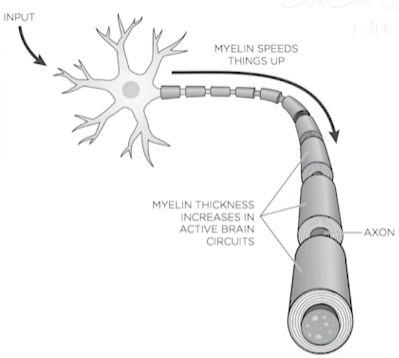

- 神经纤维

图1-4 - 髓鞘越厚,其保护轴突中的电流的效果越好